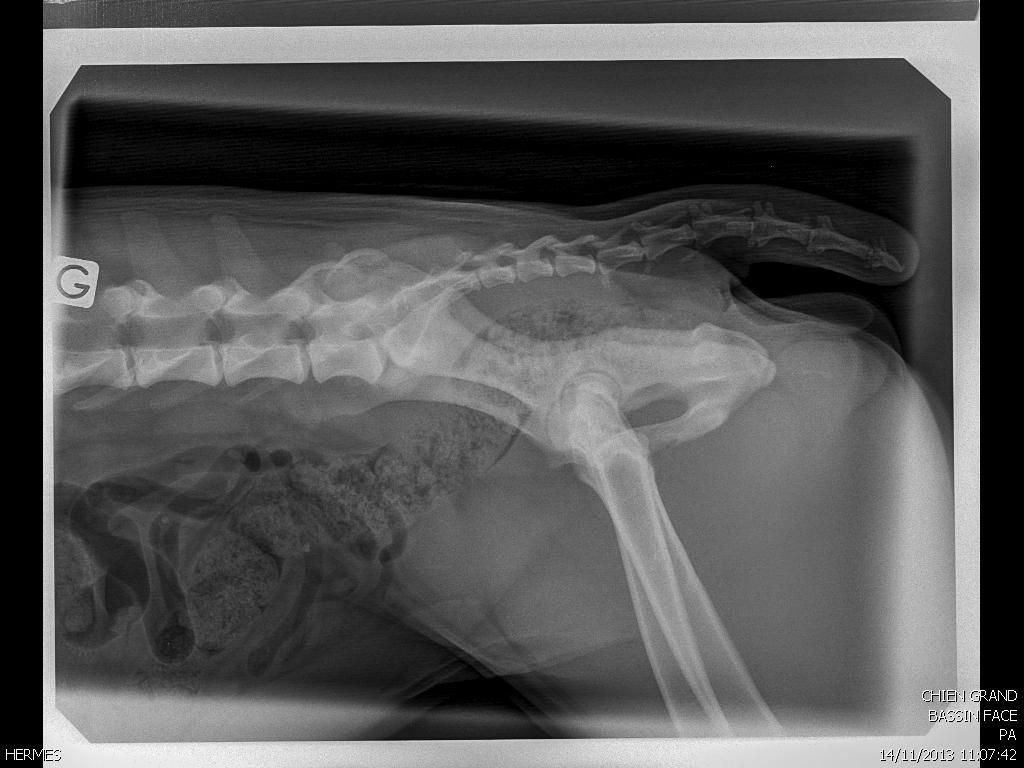

Déconnecté | Endormi pour radios |

Déconnecté | Bon debut de spondyose en L7 et S1 j'y allais pour une boiterie avant gauche et il a vu sa facon de marcher et il m'a dit qu'elle avait aussi un probleme derriere. sa n'a pas loupé. traitement d'1mois et anti inflammatoire 8 jours. pour la patte avant elle avait un blocage au coude et epaule mais pour la boiterie il dit qu'il peut y avoir une tendinite ou dechirure (dur a diagnostiquer chez le chien). 1 mois de repos pour remettre tout sa et apres selon evolution on verra. Mais je pense que je vais arreter. Je ne veux pas prendre de risque. il me l'a fortement conseiller si je voulais pas qu'elle risque d'etre HS dans 2 ans. meme si pas de probleme aux cervicales (lieu ou il y a le plus de choc en ring avec le mordant), sa raisonne jusqu'a la queue. voila. Affaire a suivre ![]() |